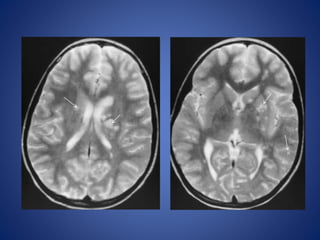

7 days old male child, with history of focal seizures.

DWI ADC

7 days oldmale child, with history of focal seizures.

• 45.